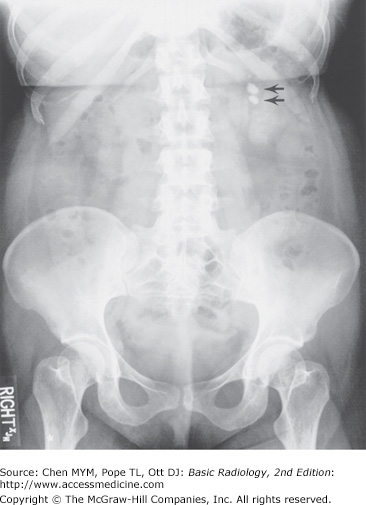

KUB shows two dense 1-cm calcifications (arrows) projecting over the mid left kidney consistent with nephrolithiasis.